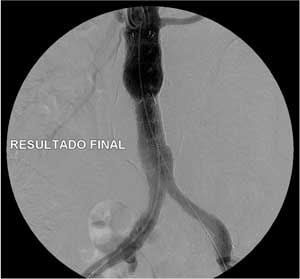

O tratamento endovascular é um alternativa muito menos invasiva que o tratamento aberto convencional, sendo realizado através de pequenas incisões na virilha. Desde que em mãos treinadas, este método apresenta baixa taxa de complicações.

A seguir segue o exemplo de um paciente tratando por via endovascular de aneurisma de aorta abdominal, e suas tomografia pré-operatória e no controle de 30 dias.

Assim, para que ocorra uma correta fixação da endoprótese na parede da aorta, é necessário liberá-la acima da origem das artérias renais. No caso a seguir, Para evitar a oclusão das artérias renais confeccionamos orifícios laterais na endoprótese (fenestração) para manter o fluxo das artérias renais. Para tanto, introduzimos um stent em cada artéria renal.